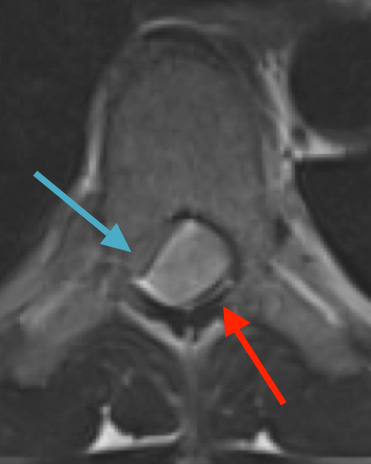

Postoperative MRI T2 illustrating the restoration of CSF surrounding the cord (blue arrow)